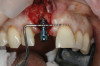

(15.) Try-in of the surgical guide prior to surgery to confirm seating and stability.

Figure 15

Prior to the initiation of the surgery, the surgical guide was tried in to confirm proper seating and stability (Figure 15). A flapless approach was not considered because the need for further bone grafting at the time of implant placement had been anticipated through the digital planning. A slightly palatal crestal incision was made, followed by two vertical incisions on the mesial and distal aspects of the edentulous site in order to preserve the papilla and avoid additional esthetic compromise to the anterior sextant. Next, a full-thickness flap was elevated to facilitate removal of the tenting screw and permit visualization of the buccal plate (Figure 16). A standard guided protocol was followed to place the implant, and its final position mirrored that of the digital plan. As predicted, the prosthetically driven implant position resulted in an insufficient buccal plate (Figure 17); therefore, additional guided bone regeneration was performed to reinforce the area and prevent future breakdown (Figure 18 and Figure 19). Making periosteal incisions could have compromised the blood supply to the flap, so instead, it was stretched in order to achieve tension free coronal advancement.31The flap was secured utilizing horizontal mattress sutures with additional supportive interrupted sutures to ensure primary closure (Figure 20). An immediate postoperative periapical radiograph (Figure 21) and CBCT scan (Figure 22) were taken, demonstrating a final implant position centered with the planned location of the gingival zenith.